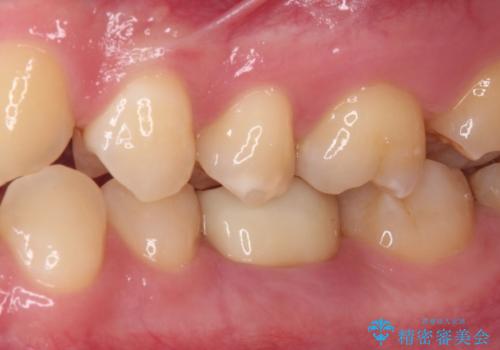

仮歯は見た目は白くても、粘着性の食事がこびりついたり、舌感がざらついていたりと、不快感を感じるだけでなく、長期装着するとむし歯が進行するリスクが高まります。

フルジルコニアクラウンを装着したことにより、舌感が改善されるとともに、むし歯再発リスクを軽減することができました。